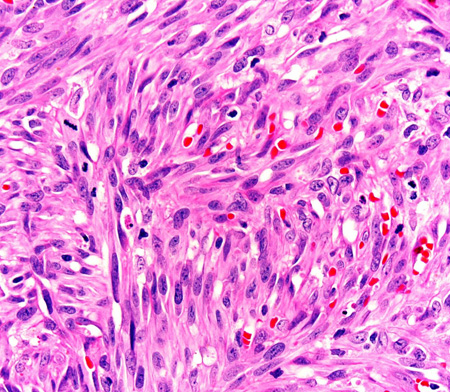

Photomicrograph of the histopathology of Kaposi's sarcoma showing fascicles of vasoformative spindle-shaped tumour cells (haematoxylin and eosin stain)

From the collection of Dr Liron Pantanowitz; used with permission